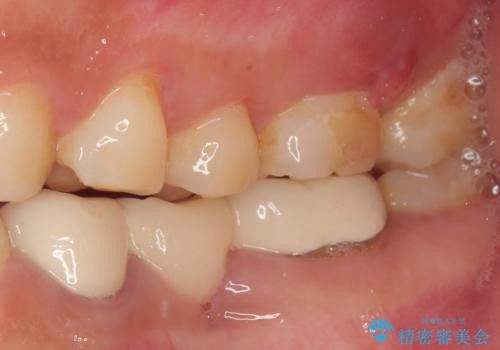

- 奥歯で咬んだときに痛みがあり、膿の出口が現れたとのことで来院された患者様です。

かかりつけ医では治療が困難と言われたとのことで当院にいらっしゃいました。

診査を行った結果、まずは根管治療を行うこととしました。

咬み合わせが非常に強く、臼歯のみに咬合力が集中している咬み合わせだったので、根管治療後はPGAクラウン(白金加金合金クラウン)にて補綴する治療計画となりました。